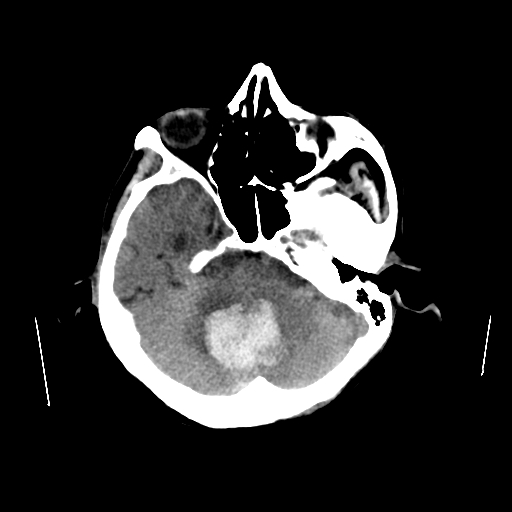

Ante la sospecha de evento vascular cerebral, se realiza tomografía cerebral simple de urgencia.

El estudio demuestra hematoma intraparenquimatoso en la fosa posterior con compromiso del vermis cerebeloso y extensión al hemisferio cerebeloso derecho, con dimensiones aproximadas de 39 × 40 × 35 mm. La lesión se acompaña de edema perilesional y produce leve compresión sobre las estructuras del tallo cerebral, así como discreta compresión del cuarto ventrículo.

Adicionalmente, se identifica hematoma intraparenquimatoso subcortical en la región parietal derecha que mide aproximadamente 12 × 11 × 16 mm, el cual muestra leve incremento de tamaño en comparación con el estudio previo.

Este caso ilustra una hemorragia cerebelosa aguda con efecto compresivo sobre el tallo cerebral en un paciente con enfermedad cerebrovascular crónica avanzada, situación que representa una urgencia neurológica debido al riesgo de deterioro rápido por compromiso de estructuras vitales en la fosa posterior. La tomografía computarizada constituye el método de elección para la detección rápida de hemorragias intracraneales y la evaluación del efecto de masa asociado.